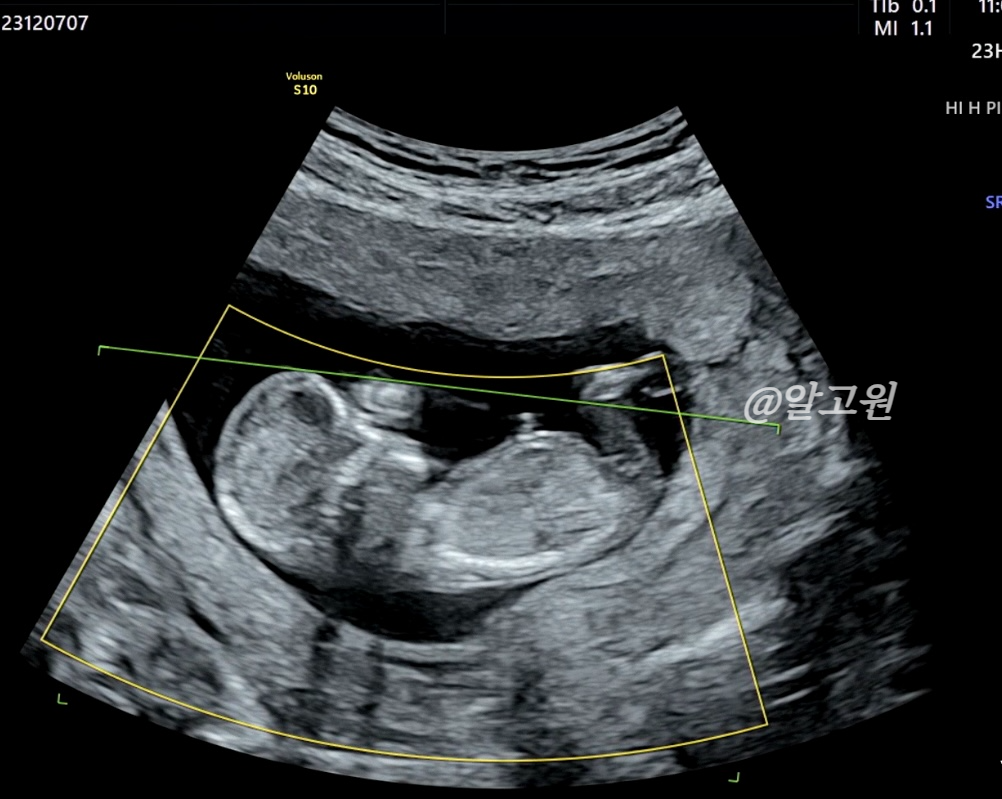

초음파로 목투명대, 척추와 뼈, 장기, 뇌 모양, 심장박동소리, 태반 위치 등

선생님께서 아주 꼼꼼히 봐주십니다.

다행히도 유동이는 정상,정상,정상!

목투명대도 1mm로 정상수치에 들었어요.

(3mm 이하면 정상, 이상일 경우 추가 검사진행)